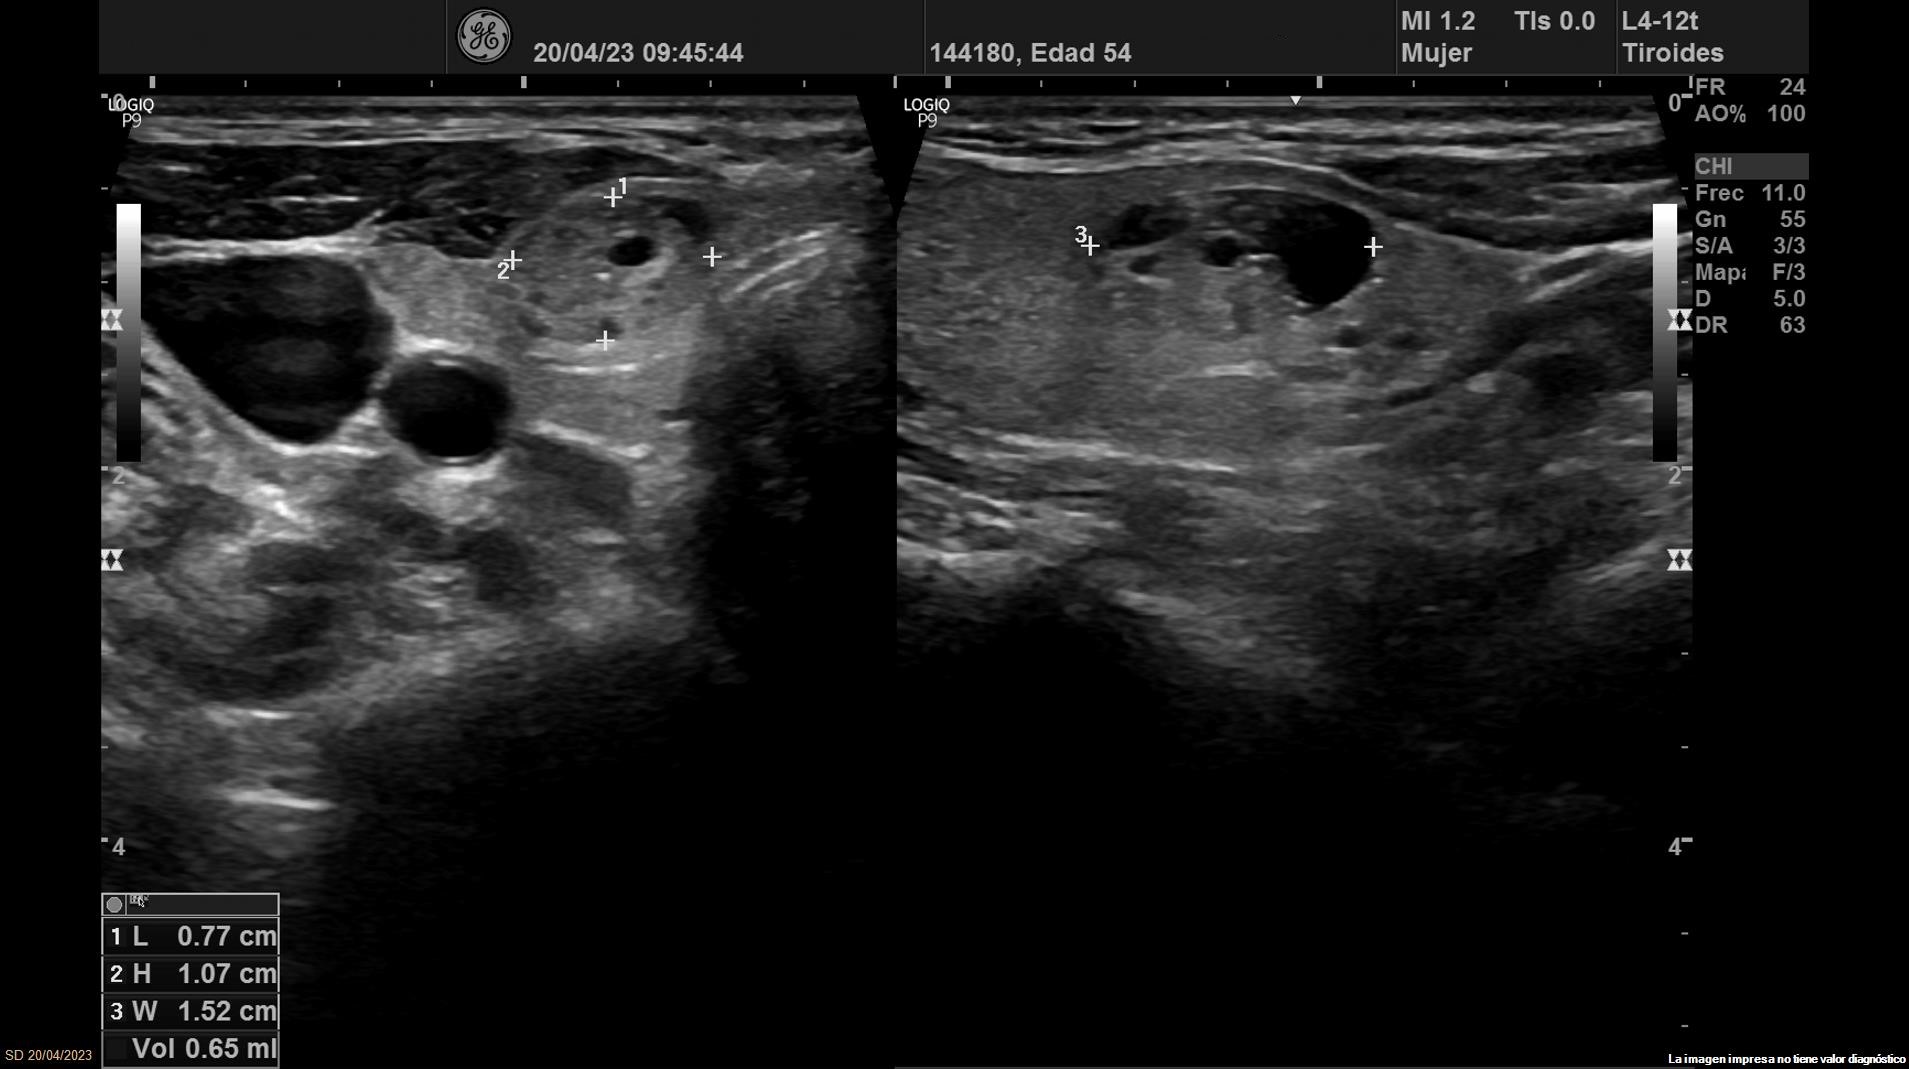

Se objetiva una adenopatía de 0,8 cm de aspecto benigno, ovalada y con bordes definidos. Además, se realiza ecografía tiroidea:

• Lóbulo tiroideo derecho: tamaño normal. En tercio inferior nódulo único espongiforme con área quística inferior que mide 15 mm de diámetro mayor longitudinal (ATA: baja sospecha).